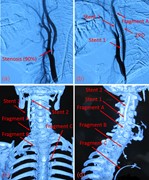

Surgical management for retained distal embolic protection device and fractured guidewire after carotid artery stenting

Tongxun Li and others

Journal of Surgical Case Reports, Volume 2016, Issue 6, June 2016, rjw105, https://doi.org/10.1093/jscr/rjw105